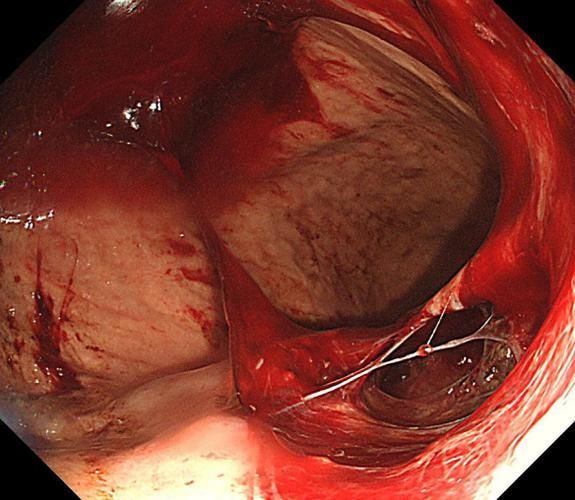

天后,云云的疼痛不仅未缓解,反而愈发剧烈,并伴随频繁呕吐。就医后,她被确诊为急性胰腺炎。经过医生为其置入的“鼻-空肠营养管”治疗,以及一段时间的恢复,云云最终康复出院。